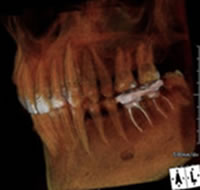

特に、インプラント治療において今やCT分析は必須です。顎骨の状態、神経、血管の走行など従来のレントゲンでは見ることのできない情報が安全性において特に重要です。当院では、より安全で精度の高い治療を提供しています。

顎骨が足りないところに埋入してしまったり、2次元のレントゲン画像だけで診断をし、オペの段階で想定外の状態であり、それに対応する技術や経験が至らなかった。。などという理由です。

CTレントゲンによる撮影と分析をきちんと行えば、失敗のリスクを激減することができます。オペの際も事前に顎の骨の状態を精密に把握できているので、術者も患者様も双方が安心して治療を行うことができ、手術の安全性を高めることができます。